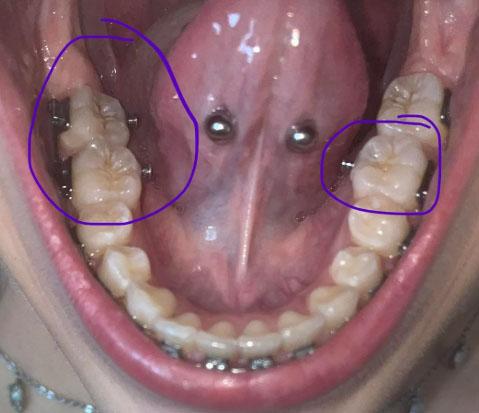

The image shows the lower jaw with molars on both the left and right sides, highlighted by circles. There are orthodontic components (brackets or attachments) present near the molars, and the chewing surfaces show plaque accumulation and early staining. The tongue piercings are visible but are not the main concern in this case.

This setup makes cleaning more difficult and increases the risk of decay around the molars.

This case shows both lower molars under orthodontic treatment, an area at high risk for decay if plaque control is poor. Regular cleaning and early prevention are essential to finish orthodontic treatment with healthy teeth.